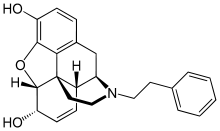

- N-Phenethylnordesomorphine

- N-Phenethylnormorphine

N-Phenethylnormorphine N-Phenethylnormorphine |